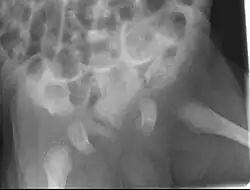

Unter dem Begriff Chondrodysplasia punctata wird eine Gruppe von zu den Chondrodysplasien zählender angeborener Erkrankungen zusammengefasst, die zu punktförmigen Verkalkungen (Kalzifizierungen) von Knorpelgewebe an Gelenken, Kehlkopf (Larynx) und Luftröhre (Trachea) führen.

Radiologisch sind die Verkalkungen lediglich bis zu einem Alter von 3 bis 5 Jahren nachweisbar. Später stehen Wachstumsverzögerungen oder -störungen im Vordergrund.